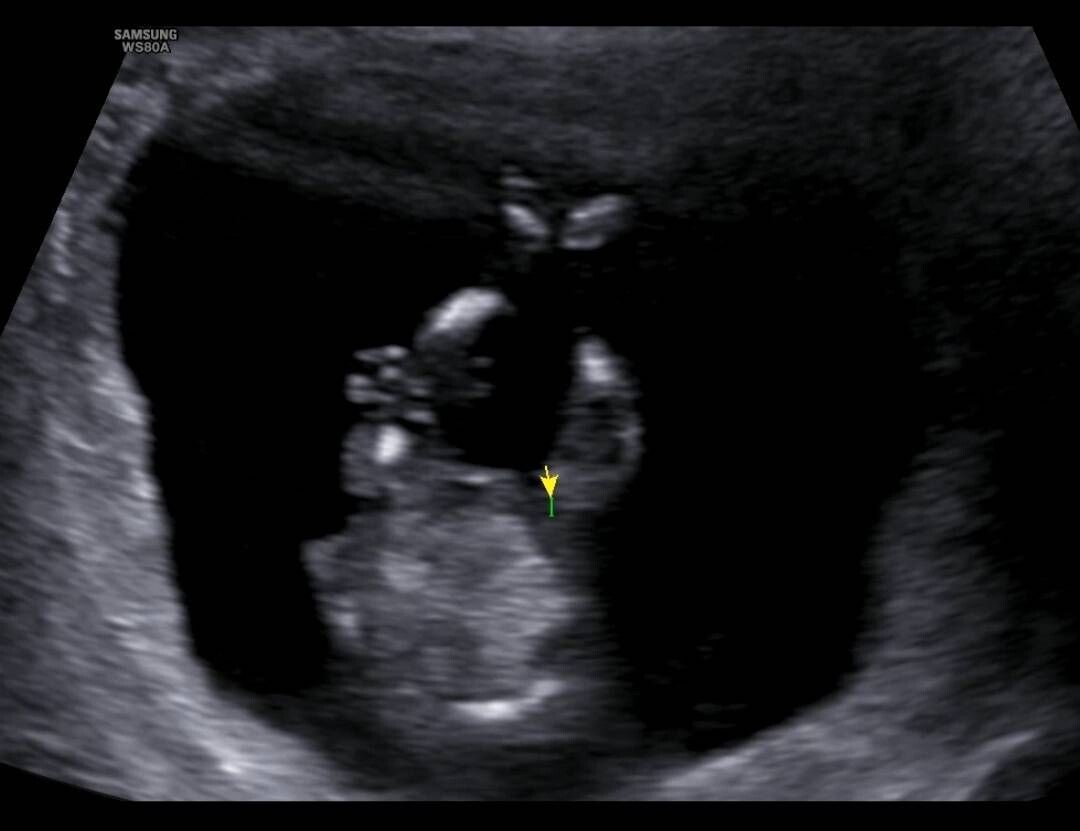

12주차 초음파 성별

뭐로보여?..

뭐가 안보여요!!!!!